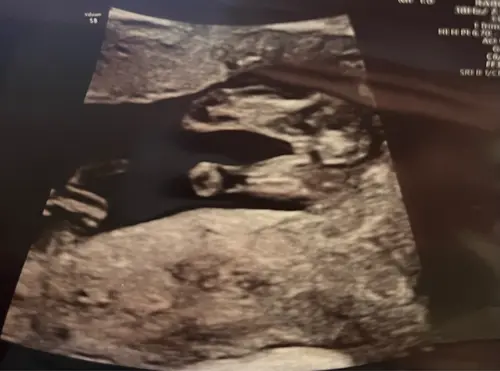

Begin van de schaamlipjes? Wat denken jullie?🥹🩷